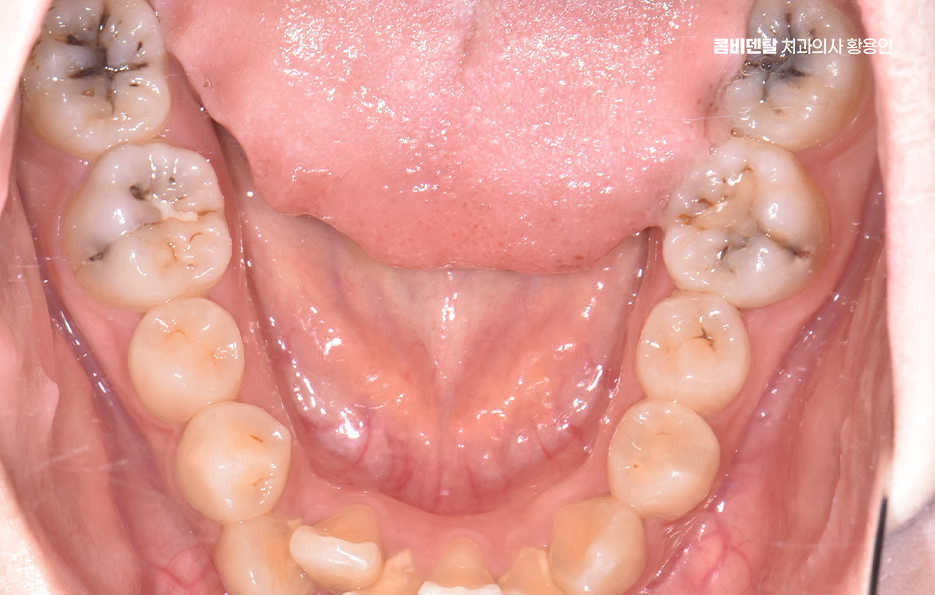

치료는 앞니 같이 신경관 수가 적고 간단한 경우에는 12번으로 끝나는 경우도 있지만, 염증이 심하거나 근관 구조가 복잡한 경우엔 34회 정도에 걸쳐 진행되기도 하며 특히 어금니처럼 뿌리가 여러 갈래로 갈라진 치아는 신경이 얇고 구불구불한 경우가 많아서, 그만큼 정밀하게 소독하고 약재를 채워 넣어야 하기 때문에 시간이 더 걸릴 수 있어요.